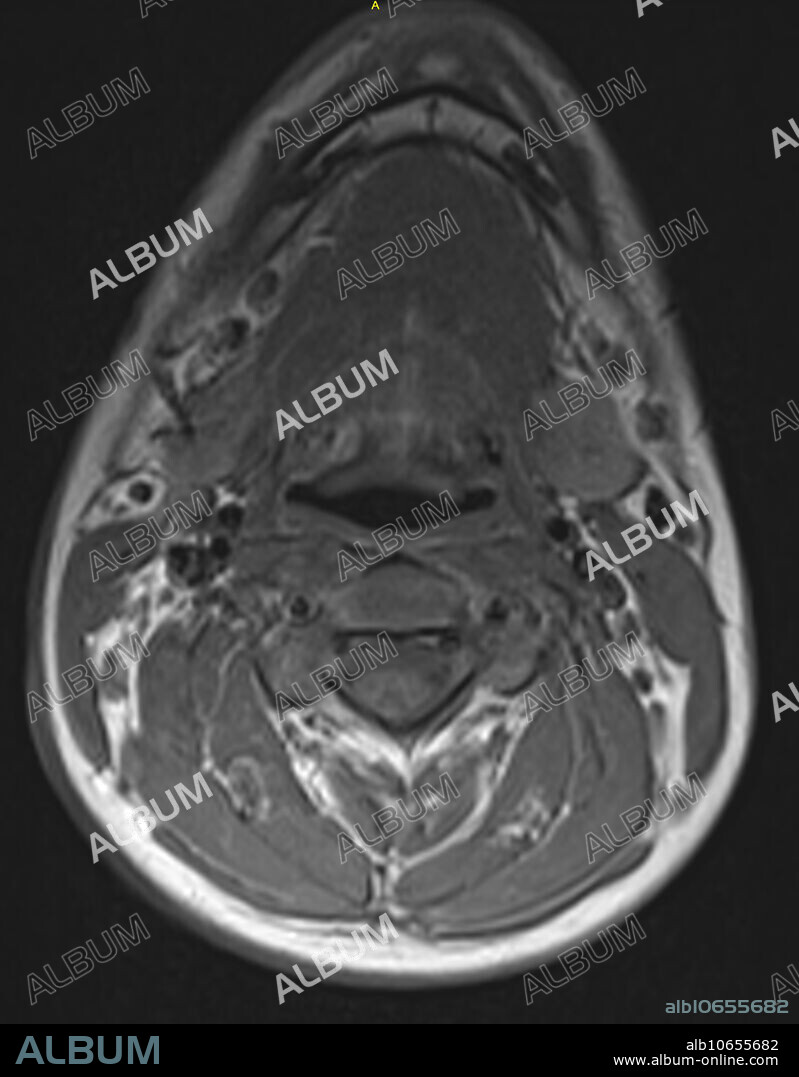

Normal neck and cervical spine, MRI

Normal neck and cervical spine, MRI

Normal T1 weighted axial MRI showing the neck and cervical spine in a 16 year old male at the level of C3.